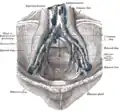

Próstata com vesículas seminais e ductos seminais, vistas de frente e por baixo.

A próstata é uma glândula exócrina do sistema reprodutor masculino. Em adultos, é do tamanho de uma noz,[1] e tem um peso médio de cerca de 11 gramas, normalmente variando entre 7 e 16 gramas.[2] A próstata está localizada na pelve. Ele fica abaixo da bexiga urinária e envolve a uretra. A parte da uretra que passa por ela é chamada de uretra prostática, que se une aos dois ductos ejaculatórios.[1] A próstata é coberta por uma superfície chamada cápsula prostática ou fáscia prostática.[3]

A classificação de "lóbulo" descreve lóbulos que, embora originalmente definidos no feto, também são visíveis na anatomia macroscópica, incluindo dissecção e quando visualizados endoscopicamente.[4][3] Os cinco lóbulos são o anterior ou istmo, o posterior, os laterais direito e esquerdo e o médio ou mediano.[8]